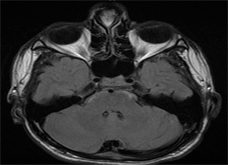

Under general anesthesia, infiltration of the dorsum of the nose was done with 1 in 100,000 lignocaine solution. Navigation protocol [Figure 3] is used because we were operating in critical area like skull base & Dura.

Figure 3. Navigation protocol.